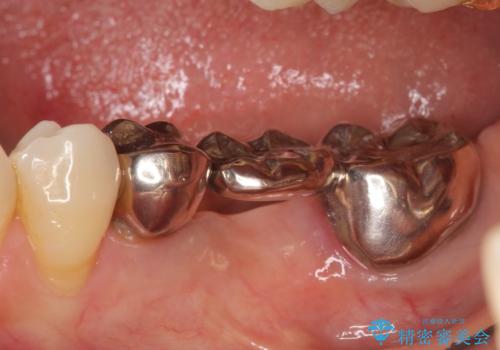

左下7の遠心部は部分的な骨欠損によるポケットが10mmあったため、再生療法による骨の再生を行いました。

骨の定着を待ちポケットが3mm(正常範囲内)であることを確認後、オールセラミッククラウンによる欠損補綴を行いました。